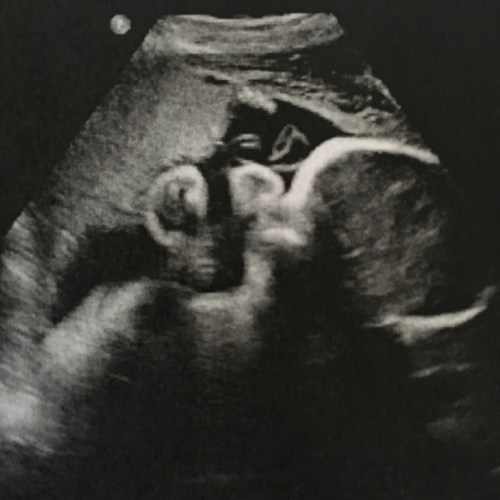

No major issues through the pregnancy, although I had colds a lot. Some nausea, compared to almost none the first time. I had a bout of continuous throwing up for 6 hours one morning, so I had to go in and get an IV. But the big thing was that the baby was breech and wasn’t turning. I went to an acupuncturist for a moxibustion treatment, which involves holding burning sticks very close to your baby toes, every day for 10 days. (It was burn-y.)

And then right around 38 weeks, I went in for the antepartum testing (that I was doing 3x a week just to monitor fluids and fetal activity as a high risk patient (because OLD)) and lo, she had turned! So the c-section was off. Waiting and seeing was back! No more surgery. But labor!